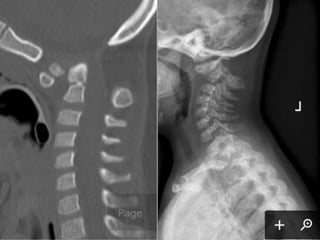

69 year old man with C2

fracture

Admitted for CHF and while

hospitalized was walking to

the bathroom at night and

fell on to head lacerating

forehead. Staff responded

to his calls for help and

immediately ordered a

cervical CT due to

complaints of new neck

pain

PMH: COPD, CHF,

anxiety/dep, liver cirrhosis,

cognitive decline,

pulmonary HTN,

SH: retired lives in group

home

69 year oldman with C2 fracture Admitted for CHF and while hospitalized was walking to the bathroom at night and fell on to head lacerating forehead. Staff responded to his calls for help and immediately ordered a cervical CT due to complaints of new neck pain PMH: COPD, CHF, anxiety/dep, liver cirrhosis, cognitive decline, pulmonary HTN, SH: retired lives in group home